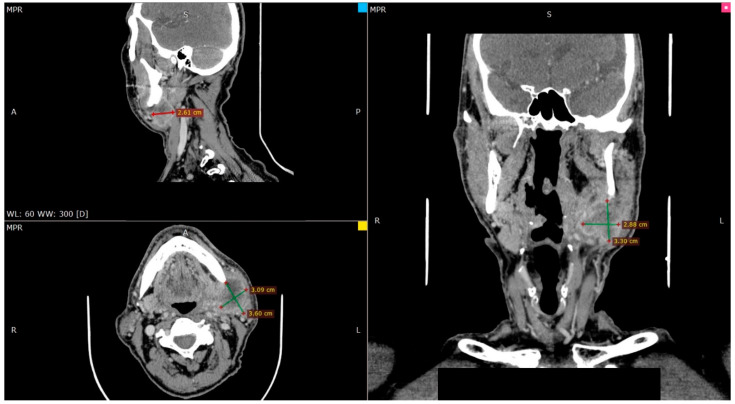

Materials and methods: A case of an 89-year-old man is reported, who initially underwent surgical and complementary treatment for neck squamous cell carcinoma of occult primary and later for tonsillar diffuse large B-cell non-Hodgkin lymphoma.

Results: The second primary was considered a recurrence in the neck of the original cancer of unknown primary, so a new surgical management was decided. The final pathology report described a diffuse large B-cell non-Hodgkin lymphoma.